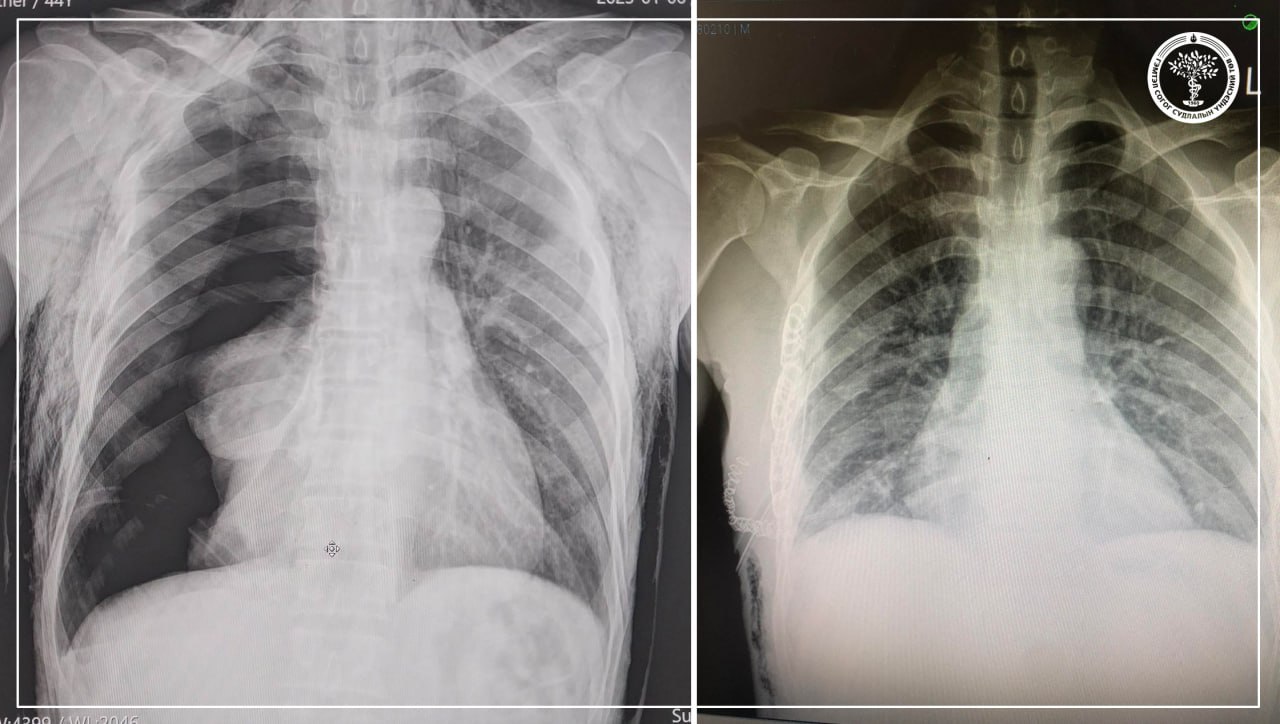

| ГССҮТ-ийн мэс заслын баг алсын дуудлагаар орон нутагт яаралтай тусламж үзүүллээ |